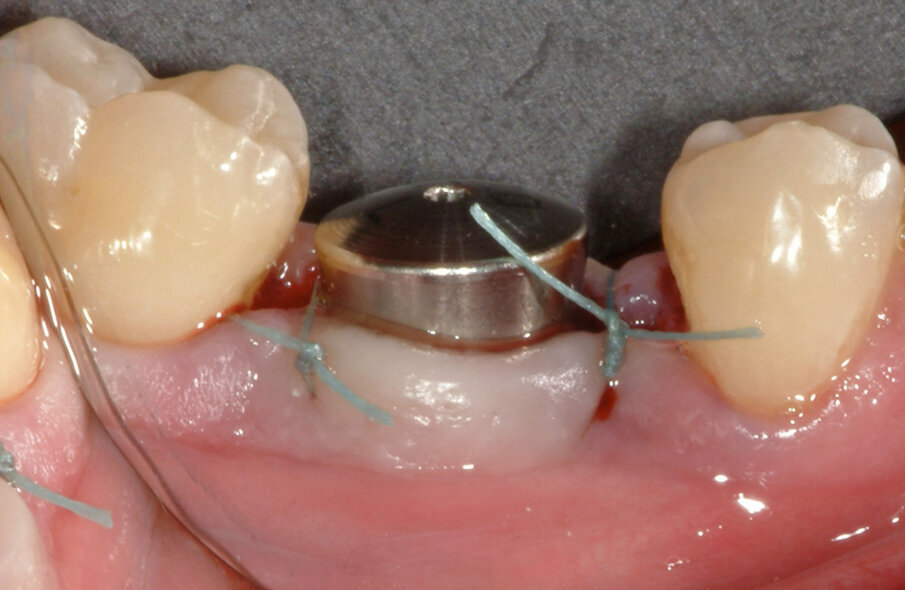

Fig. 8: A 7 mm healing abutment was placed to guide the soft tissue to an optimal healing situation.